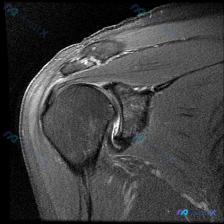

踝关节MRI读片病例分享,整理了完整分析思路 这是一例踝关节矢状位T2加权MRI,我把影像发现和分析思路整理出来,和大家一起讨论。 一、基本影像信息 这是踝关节MRI T2序列矢状位图像,可观察到胫骨远端、距骨、跟骨及周围软组织结构,核心阳性征象如下: 1. 骨骼关节改变:距骨穹窿(圆顶)可见明确局...